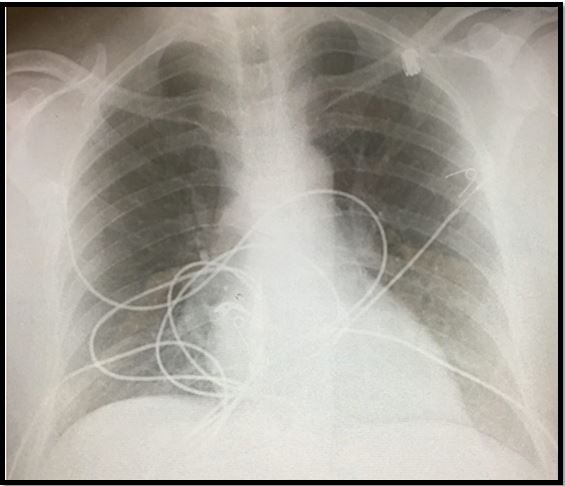

What does the case image show? It is a normal chest x-ray.

Dyspnea has a plethora of causes, but the differential diagnosis becomes narrower when hypoxia also is present. It becomes narrower still when results of chest x-ray are normal. Other ways to categorize causes of dyspnea or hypoxia are shown in the highlighted area of the sample page in the image at right, above (please click to enlarge). They include whether symptom onset is acute or chronic and whether or not hypoxia resolves with oxygen.